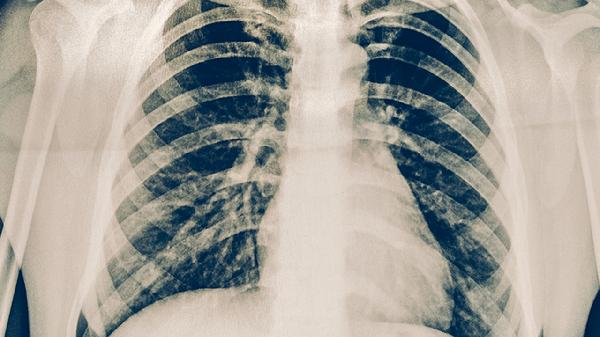

淋巴瘤確診需依靠淋巴結(jié)活檢、骨髓穿刺等檢查,結(jié)合免疫組化分型。肺癌診斷主要依靠胸部CT、支氣管鏡活檢、經(jīng)皮肺穿刺等檢查,病理確診后還需進行基因檢測。